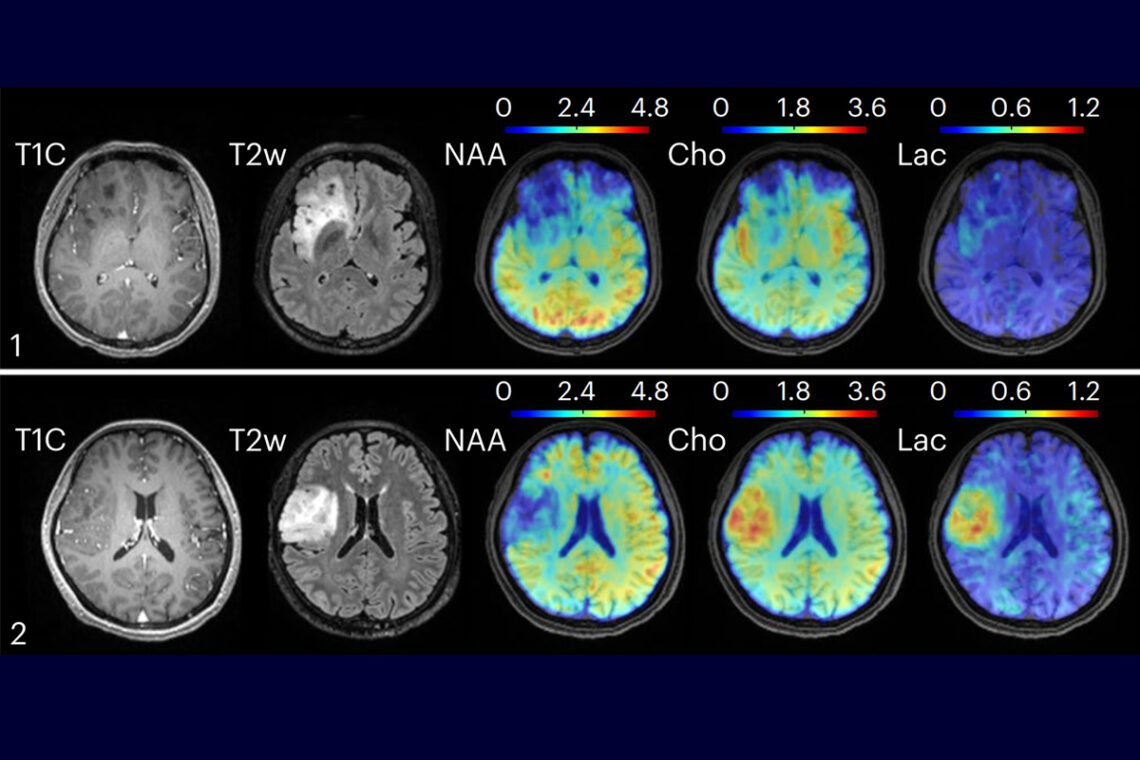

The researchers tested their MRSI technique on several populations. In healthy subjects, the researchers found and mapped varying metabolic and neurotransmitter activity across different brain regions, indicating that such activity is not universal. In patients with brain tumors, the researchers found metabolic alterations, such as elevated choline and lactate, in tumors of different grades — even when the tumors appeared identical on clinical MRI images. In subjects with multiple sclerosis, the technique detected molecular changes associated with neuroinflammatory response and reduced neuronal activity up to 70 days before changes become visible on clinical MRI images, the researchers report.